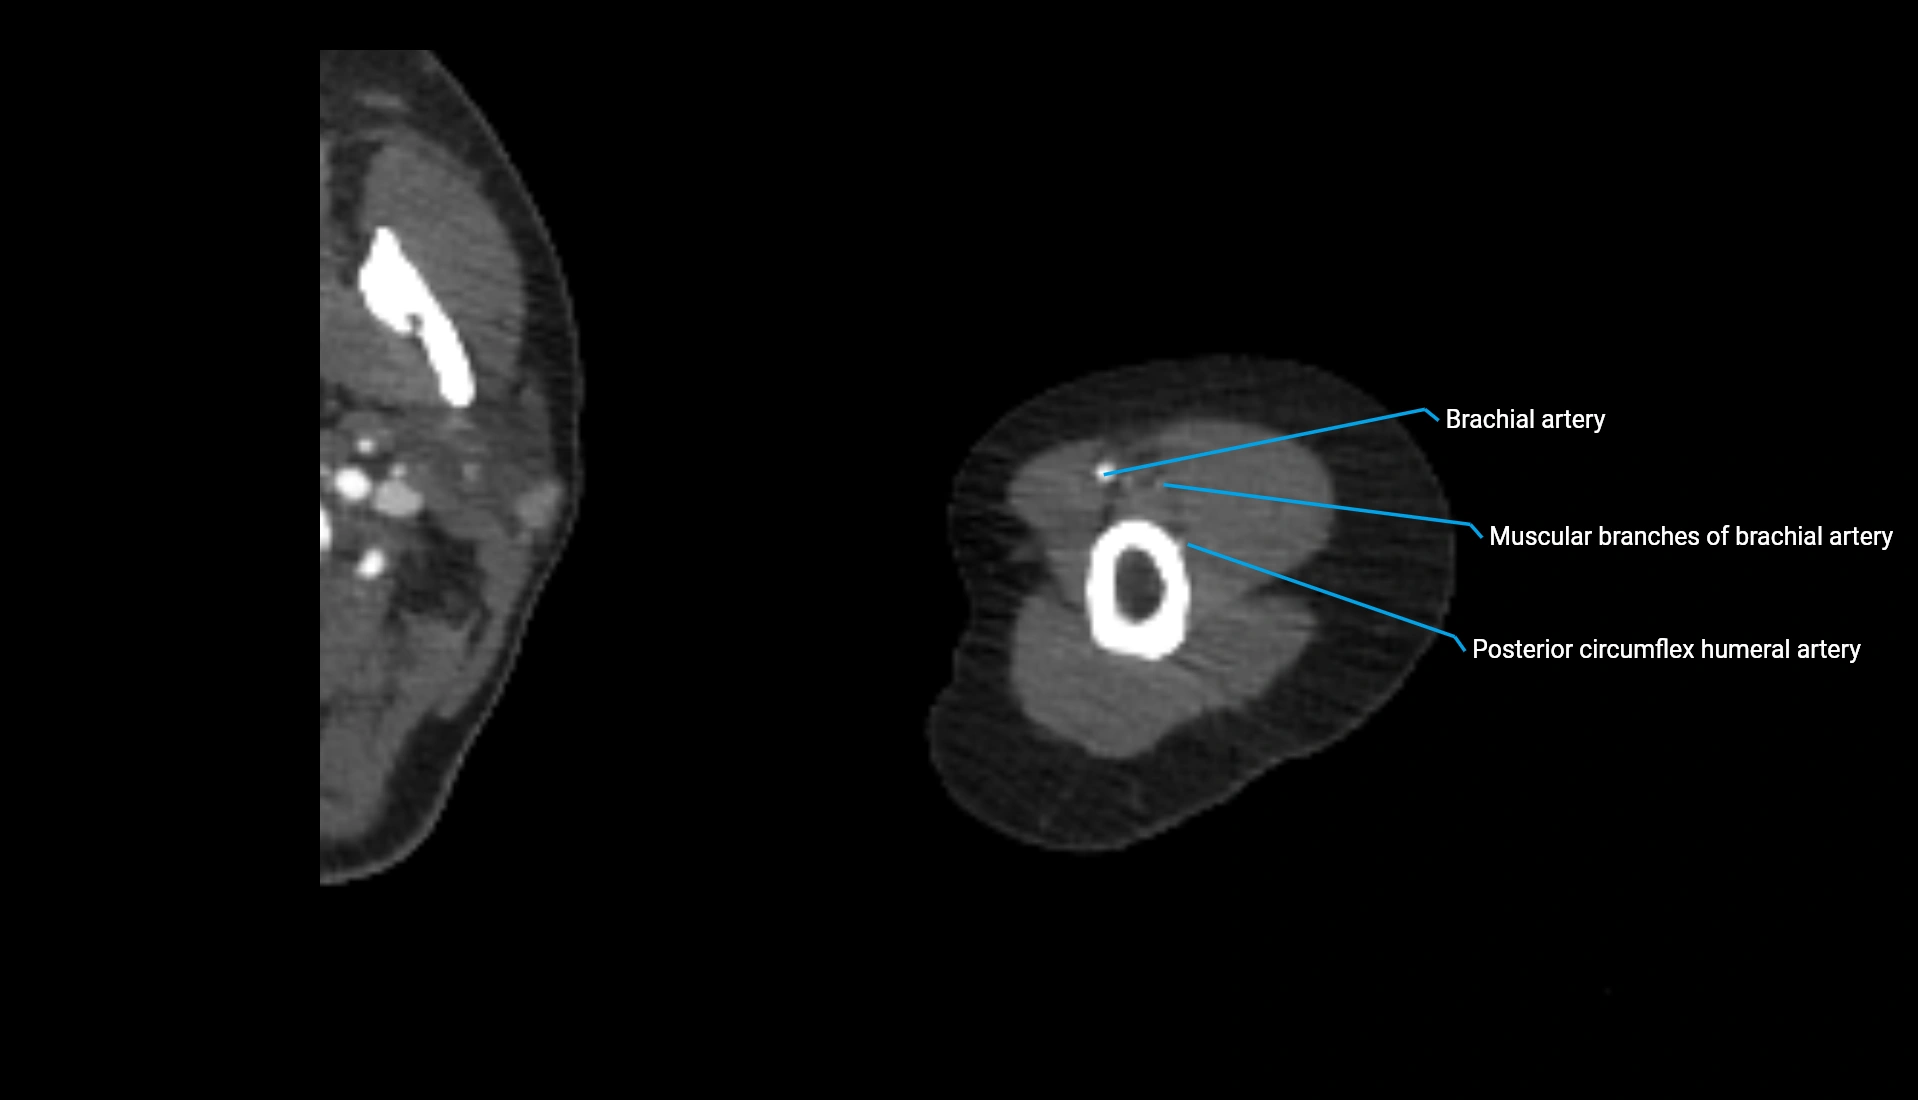

CT Appearance

Non-Contrast CT:

• Cortex: High-density, sharply defined

• Subchondral bone: Dense cancellous matrix

• Articular surface: Smooth concave contour articulating with the capitellum

• Excellent for evaluating bone integrity, alignment, and subtle fractures

Post-Contrast CT:

• Bone: No enhancement

• Joint capsule and synovium: Mild enhancement outlining the joint

• Improves contrast between soft tissues and bony margins

• Useful in detecting subtle joint abnormalities or postoperative changes